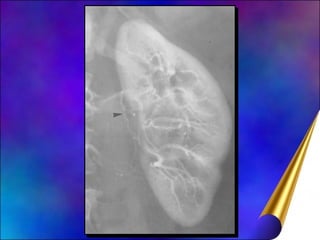

Diagnóstico Anemia (30%) Hematúria (60%) Ultra-sonografia Urografia excretora (calcificação) Tomografia computadorizada Alta sensibilidade e especificidade Ressonância magnética Radioisótopos (rastreamento de metástases ósseas) Arteriografia renal (angioressonância)

Diagnóstico Anemia (30%)Hematúria (60%) Ultra-sonografia Urografia excretora (calcificação) Tomografia computadorizada Alta sensibilidade e especificidade Ressonância magnética Radioisótopos (rastreamento de metástases ósseas) Arteriografia renal (angioressonância)